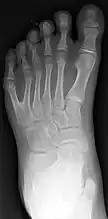

Classification is performed by using x-ray imaging to see the bone structures.[17] In 1961, Frantz and O’Rahilly proposed that congenital anomalies of the limb could be classified in seven categories, based on the embryonic failure causing the clinical presentation. These categories are failure of formation of parts, failure of differentiation, duplication, overgrowth, undergrowth, congenital constriction band syndrome, and generalized skeletal abnormalities.[36] In 1976 this was modified by Swanson.[37] Polydactyly belongs to the category of duplication.[12] As of 2009, research has shown that the majority of congenital anomalies occur during the 4-week embryologic period of rapid limb development.[12]

X-ray of type III central polydactyly. The middle fingers are the same length.